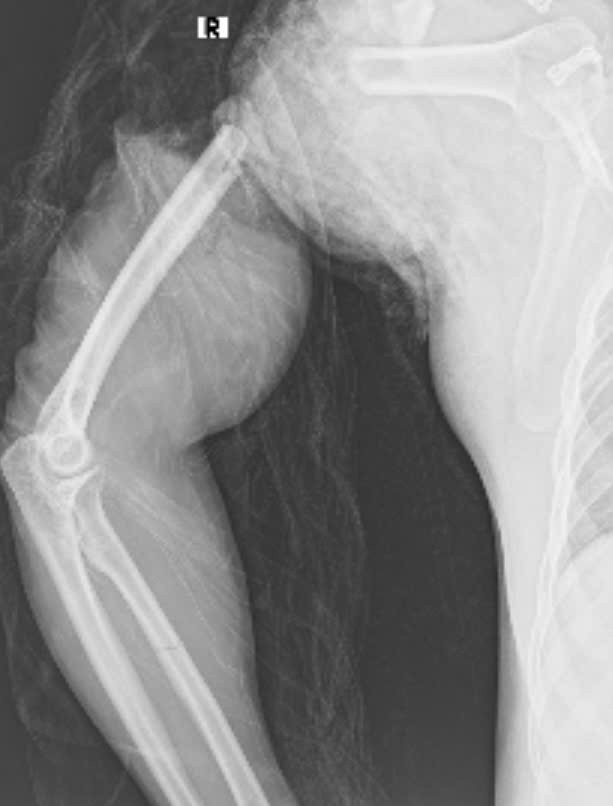

Cánh tay sau nối trên phim chụp - Ảnh BVCC